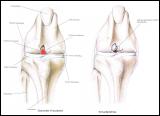

Der Kreuzbandriß beim Hund ist im Gegensatz zum Menschen in 90 % der Fälle nicht durch einen Unfall verursacht sondern eine Folge von degenerativen Prozessen im Gelenk wie z. B. einer Gelenksarthrose. Begünstigt wird diese Erkrankung z. B. durch Übergewicht. Deshalb geht der betroffene Hund meistens ohne deutlich erkennbare Ursache plötzlich lahm. Beim Neufundländer und Boxer ist eine genetische Anlage bewiesen. Generell gilt aber, dass vor allem ältere kastrierte Hündinnen (> 6-7 J) mit Übergewicht betroffen sind. Die betroffenen Tiere zeigen eine zumeist deutliche Lahmheit am betroffenen Hinterbein. Die Diagnose wird beim Tierarzt durch eine Ganganalyse, den Sitztest, eine umfassende klinische Untersuchung (z. B. Schubladenphänomen, Tibiakompressionstest) und Röntgendiagnostik gestellt. Eine Röntgenuntersuchung in mind. 2 Ebenen ist zwingend erforderlich um weitere Erkrankungen (z.B. eine Arthrose oder eine OCD) festzustellen.

Arthrose im Knie